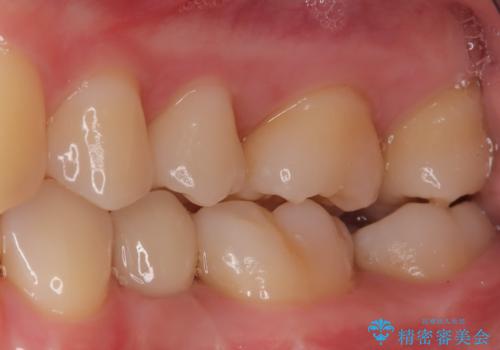

小臼歯のインプラント

- 20代女性

- 6ヶ月

- 小臼歯が先天性欠損していたため、インプラントにて補綴しています。